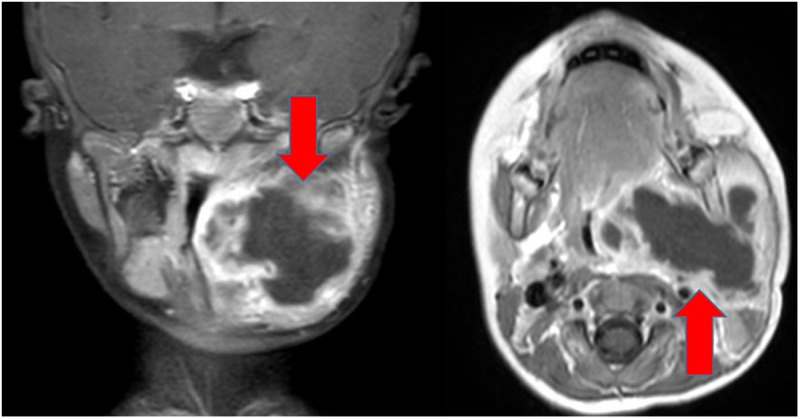

背景:扁桃体周围脓肿(PTA)是耳鼻喉科专家和儿科初级保健提供者普遍存在的感染,有可能导致严重的并发症。本研究的目的是探讨小儿腹膜周围脓肿的手术治疗,并比较双侧手术与单侧手术的风险概况。此外,对术中获得的微生物涂片的评估应提供计算的抗生素治疗是否充分覆盖微生物谱的信息。方法:我们对2009年至2024年间接受单侧扁桃体切除术(UTE)或双侧扁桃体切除术(BTE)治疗PTA的儿童患者(n = 150)进行回顾性分析。对患者病历进行分析,包括出血风险、其他并发症的发生、UTE的复发率以及微生物菌群和抗生素治疗情况。结果:两组术后出血无明显差异。在接受UTE治疗的患者中,有4.4%的患者发现PTA复发。术后未见其他严重并发症。抗生素治疗主要依靠头孢呋辛和氨苄西林舒巴坦,符合检测到的微生物菌群。结论:在儿科患者中,UTE和BTE的并发症发生率无相关差异。根据检测到的微生物菌群使用广谱抗生素。自2019年以来,氨苄西林-舒巴坦的计算抗生素治疗一直是儿科PTA的首选治疗方法。